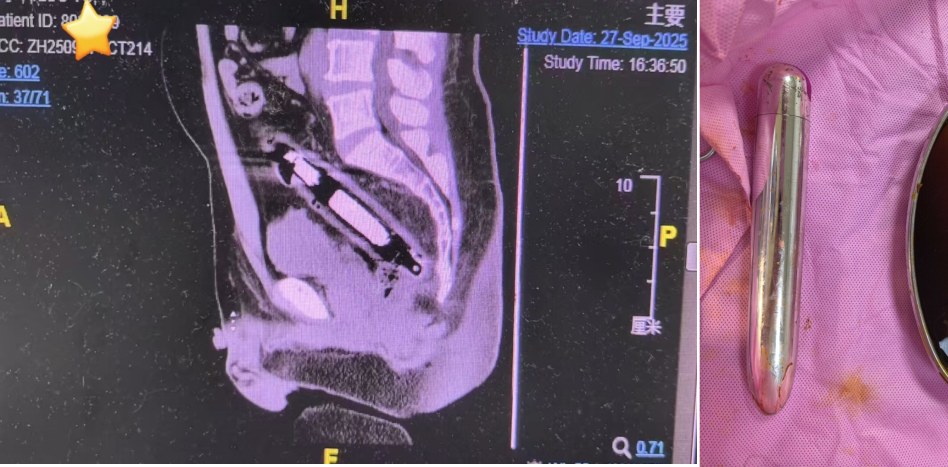

王先生的ct图及取出的异物图。

长沙市中医医院肛肠科副主任医师李心茹检查确定该异物为近20厘米长的圆柱状金属物。考虑到金属物质坚硬,若不及时取出,极有可能扎破肠道引发穿孔,治疗团队当即为王先生制定紧急手术方案。在快速完善各项术前准备、麻醉成功后,手术当日顺利开展。最终,医生成功将金属异物取出,术后王先生恢复良好。